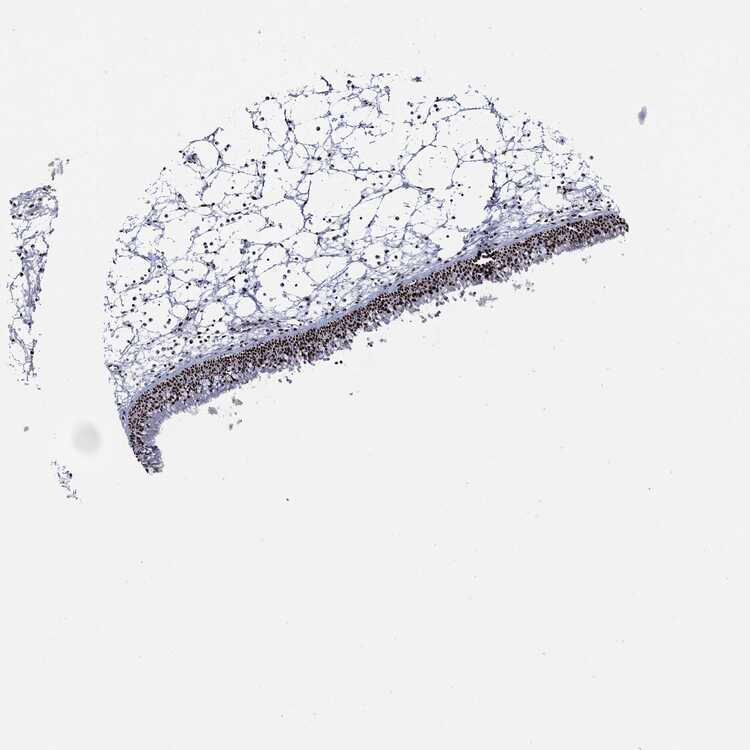

TISSUE PRIMARY DATA NASOPHARYNX Show tissue menu

NASOPHARYNX - Antibody stainingi

Antibody staining in the annotated cell types in the current human tissue is reported as not detected, low, medium, or high, based on conventional immunohistochemistry profiling in selected tissues. This score is based on the combination of the staining intensity and fraction of stained cells.

Each image is clickable and will lead to virtual microscopy that enables deeper exploration of all samples and also displays staining intensity scores, fraction scores and subcellular localization as well as patient and tissue information for each sample.

Antibody HPA030521Antibody HPA030522Antibody HPA030523Antibody CAB080240Antibody CAB080241Antibody CAB080242

Basal cells --Low---

Ciliated cells (cell body) --Not detected---

Ciliated cells (cilia axoneme) --Not detected---

Ciliated cells (ciliary rootlets) --Not detected---

Ciliated cells (tip of cilia) --Not detected---

Goblet cells --Not detected---

Respiratory epithelial cells LowHigh-MediumHighHigh